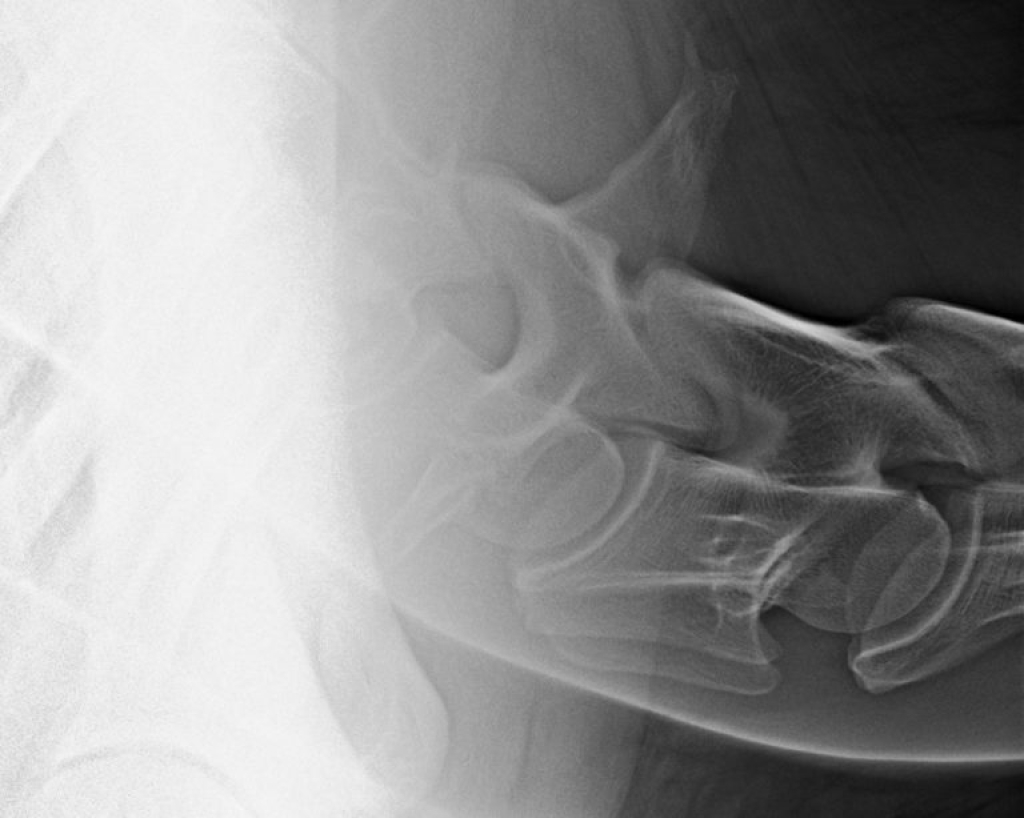

Links: Facetgewricht röntgen

Rechts: Uitprojectie facetgewricht

Facetgewricht röntgen

Uitprojectie facetgewricht

Het klinische onderzoek kunnen we aanvullen met beeldvorming. Op röntgenopnamen kunnen we de facetgewrichten van de gehele hals beoordelen, bij een zijdelingse opname zien we echter beide facetgewrichten over elkaar heen geprojecteerd. Om deze apart te kunnen beoordelen kunnen we “schuine” foto’s maken, ofwel uitprojecties.